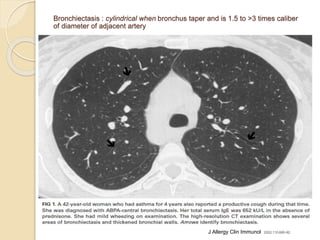

Bronchiectasis : cylindrical when bronchus taper and is 1.5 to >3 times caliber

of diameter of adjacent artery

J Allergy Clin Immunol 2002;110:685-92.